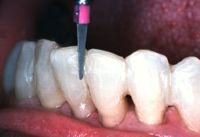

El composite se coloca en el canal lingual utilizando la punta de los carpules, el composite fluirá suavemente dentro del mismo.

Ribbond se inserta dentro del canal relleno de composite comenzando por el extremo distal del canal o el canino, presionando la fibra Ribbond dentro del composite. Al realizar este procedimiento el sobrante de composite rebasara. Se alisara y retirara el exceso de las superficies linguales antes de polimerizar. Se polimerizara las superficies linguales durante 60 segundos por diente.

Después de retirar cualquier irregularidad del composite polimerizado, las superficies de la restauración suavizarse. Esto se logra con una resina de composite fluido dispensado con una jeringa con punta de aguja. Se polimerizara la superficie lingual durante 40 segundos por diente.